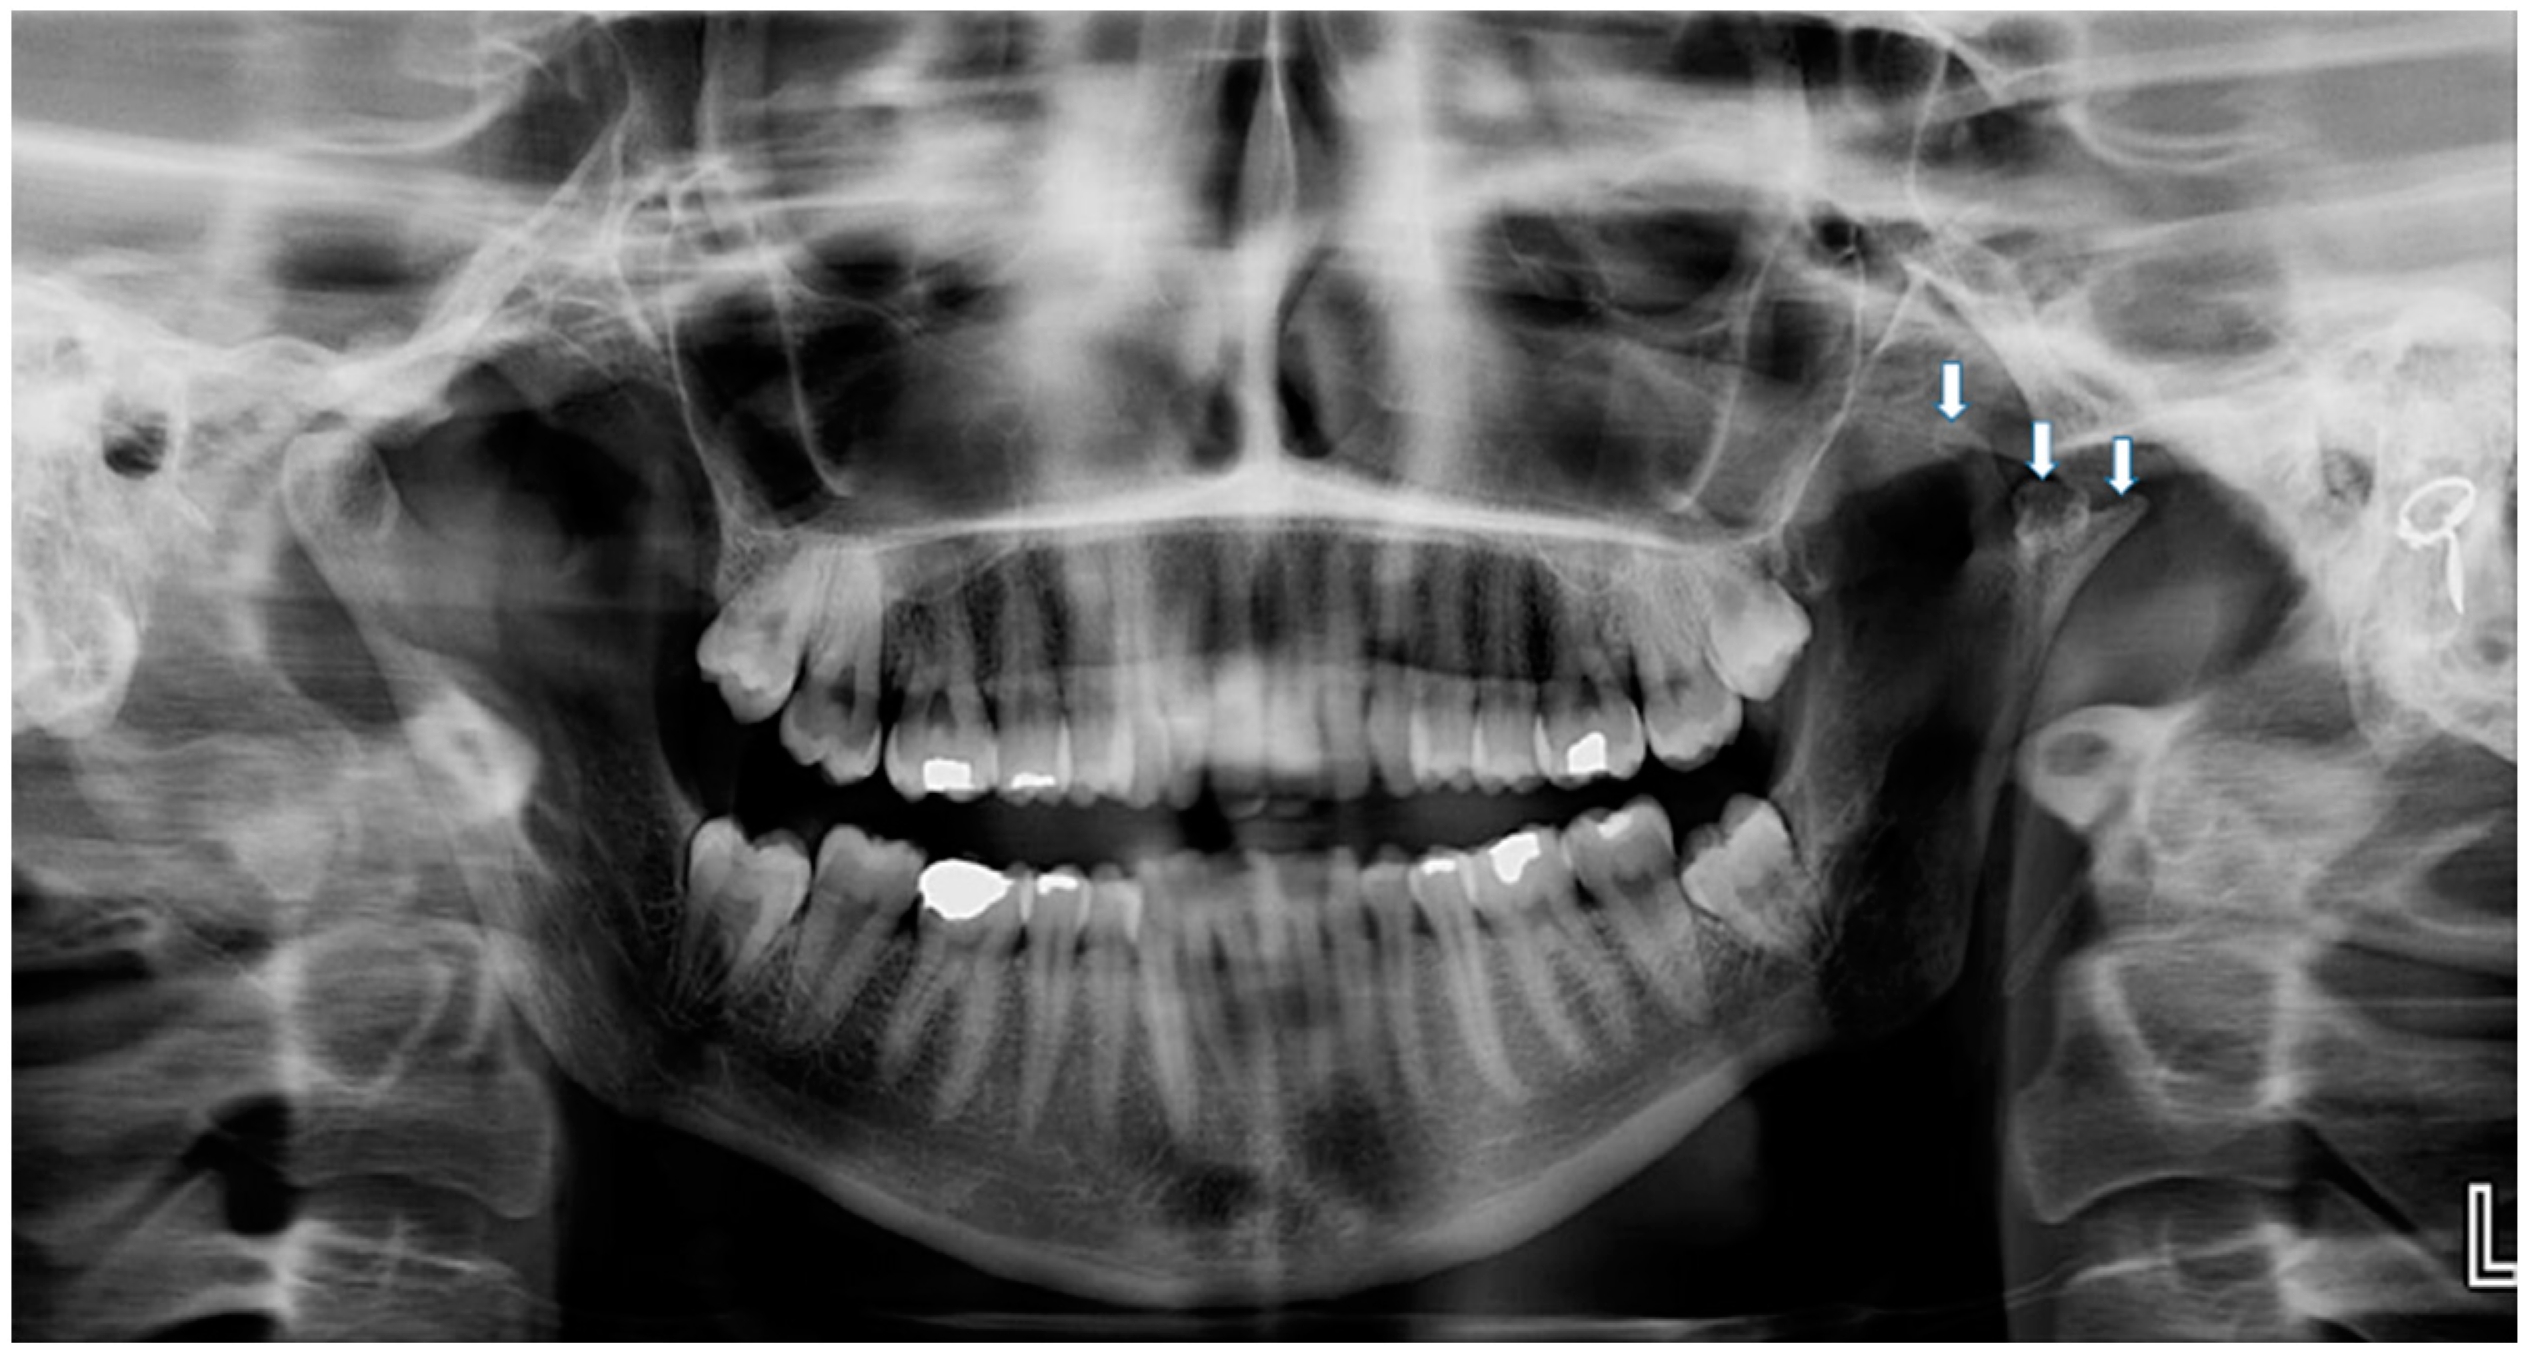

| Sezgin & Katipman 2009 [3] | M, 31 | Mandible deviated to the right | Trauma | FU | - |

| Prasanna T. et al., 2015 [1] | F, 26 | Mild facial asymmetry, micrognathia & deviation of the mandible to left | - | None | - |

| Hernández-Andara A. et al., 2017 [8] | M, 12 | Facial asymmetry & a clicking noise in the left TMJ | Trauma | FU | - |